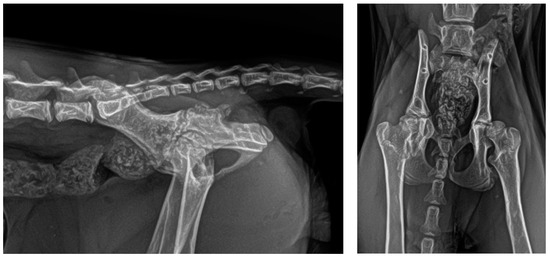

2.4. Follow-Up

3. Results